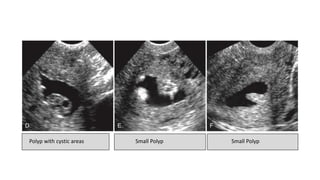

• Sonohysterography

-Polyps are best seen at

sonohysterography

-appear as echogenic, smooth,

intracavitary masses outlined by fluid

Sonohysterogram confirms polyp (arrow)

and thick endometrium (arrowheads)

caused by hyperplasia.

Polyp with cystic areas Small Polyp Small Polyp

• Hysterosalpingography

Polyp with cysticareas Small Polyp Small Polyp